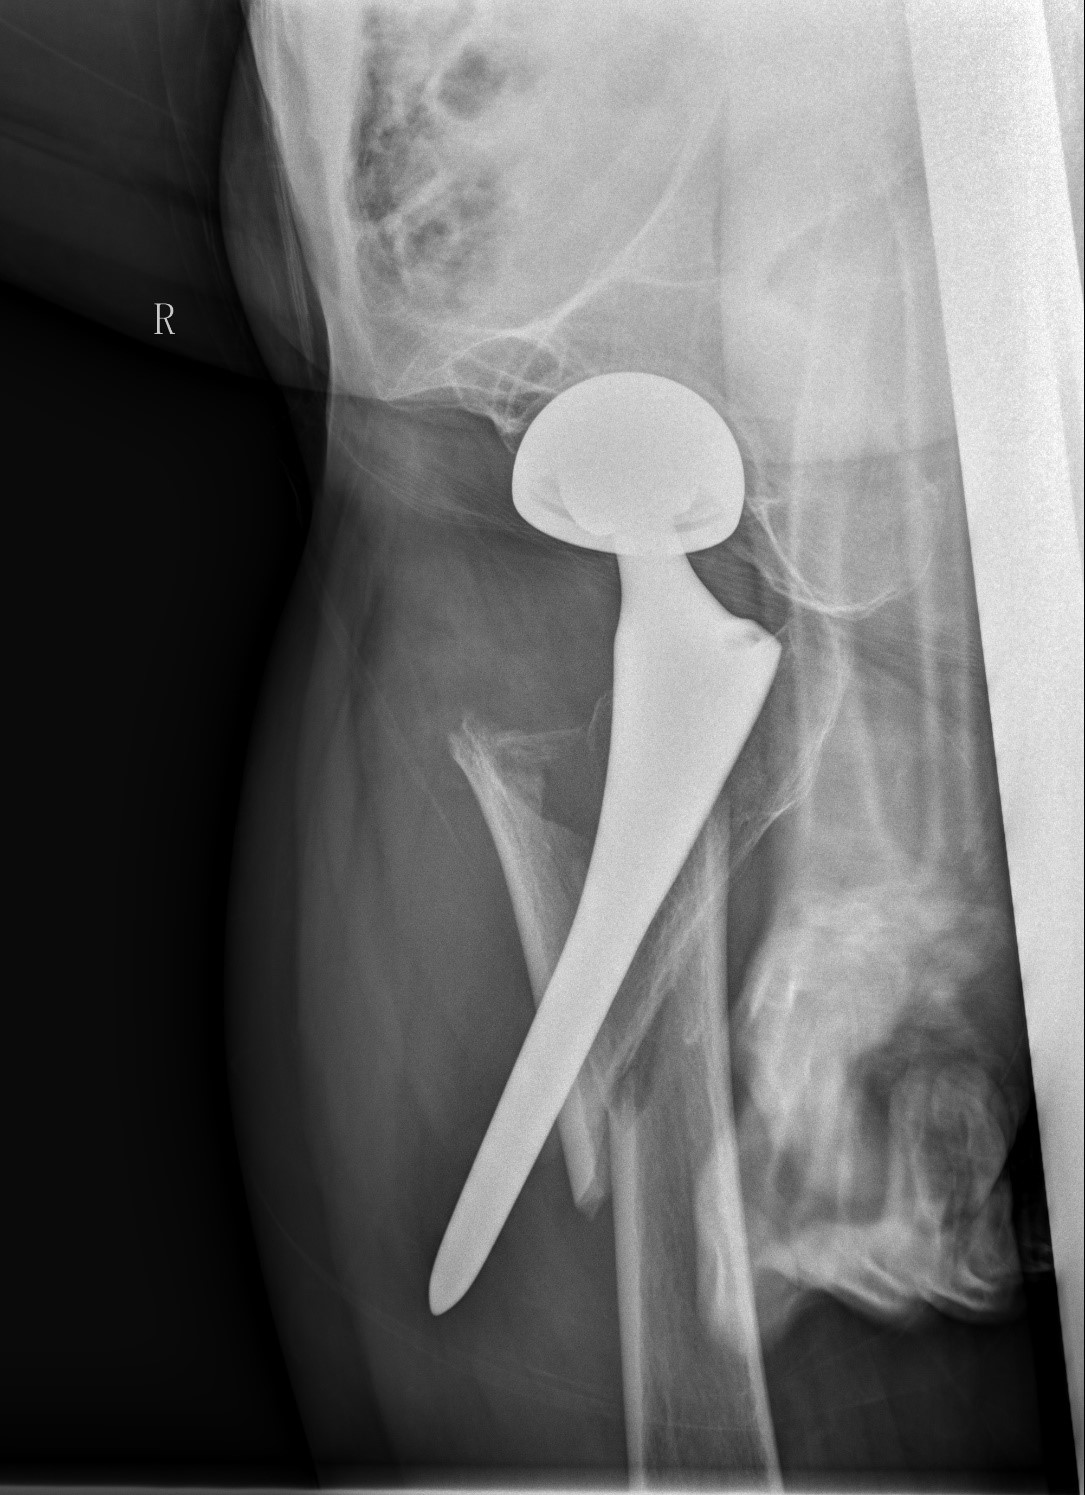

案例三:59岁女性假体周围骨折

患者情况:吴女士,5年前曾在金瓶梅电影接受人工髋关节置换术,近日因在家中地板湿滑处摔倒,导致假体周围骨折。

治疗难点:

1.摔伤后需评估假体是否松动;

2.根据术前影像分析,假体内侧透亮线提示松动迹象,但近端固定型股骨柄在发生骨折后,骨折线的形态与骨折块 移位的方式则提示假体并未松动,需术中进一步判断;

3.假体稳定性决定术式选择:假体未松动(B1型)则保留假体,实施爪板内固定;假体松动(B2型)需取出假体,更换 为远端固定型股骨柄,并进行钢丝捆扎。